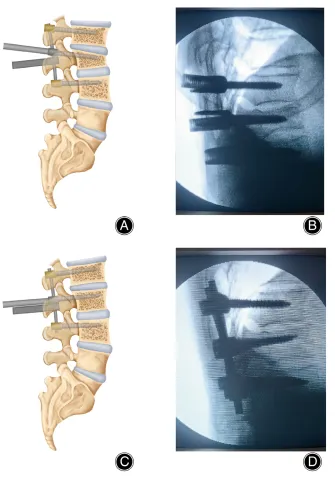

This is where ‘icotec’ comes in with their BlackArmor® - Carbon-fibre reinforced PEEK pedicle screw and cage systems. Manufactured through their proprietary composite flow moulding and Ti-iT titanium coating, they claim rapid osseointegration, radiolucency, and most importantly allowing Radiotherapy behind it.

KONG®-TL VBR System – Expandable VBR cage appeared to keep surrounding structures well visible in post-op imaging for radiotherapy and planning further treatment.

KONG®-TL VBR System